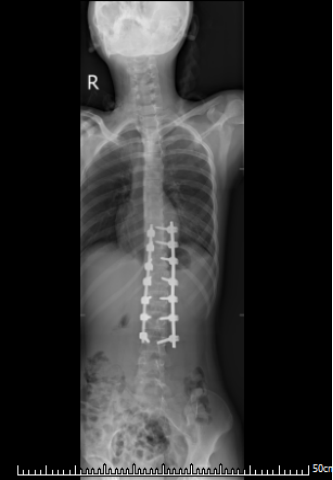

甜甜术后脊柱DR影像

主管医生李东东副主任医师积极完善术前准备后,陈光友主任中医师、李东东副主任中医师、姜铧财副主任医师及手术室、麻醉科医护团队经过4小时左右的手术,甜甜的脊柱侧弯畸形基本矫正,术中出血400ml,伤口采用皮内美容缝合,切口虽长却不会留下难看的疤痕。

术后4天,在胸腰支具的保护下,甜甜能自行下地活动,下肢感觉及运动功能完好,身高较术前增加了4cm,成为了真正的花季美少女。

患者术后身高增加4cm